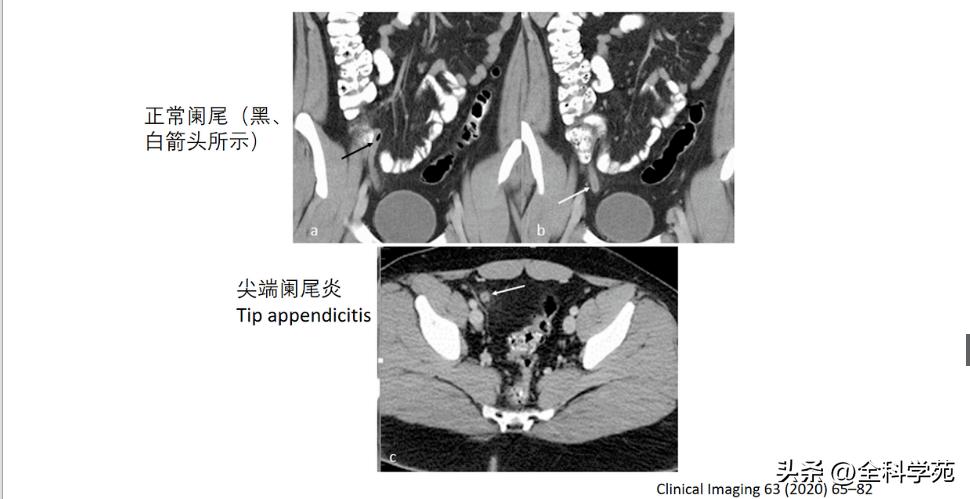

◆ 假阴性

尖端阑尾炎、臀部阑尾炎(残余阑尾组织大于5mm,0.15%),右下腹脓肿

▶ Normalappendix(正常阑尾,Type 0)